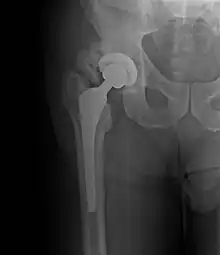

| Heterotopic ossification around the hip joint in a patient who has undergone hip arthroplasty |

Heterotopic ossification of varying severity can be caused by surgery or trauma to the hips and legs. About every third patient who has total hip arthroplasty (joint replacement) or a severe fracture of the long bones of the lower leg will develop heterotopic ossification, but is uncommonly symptomatic. Between 50% and 90% of patients who developed heterotopic ossification following a previous hip arthroplasty will develop additional heterotopic ossification.